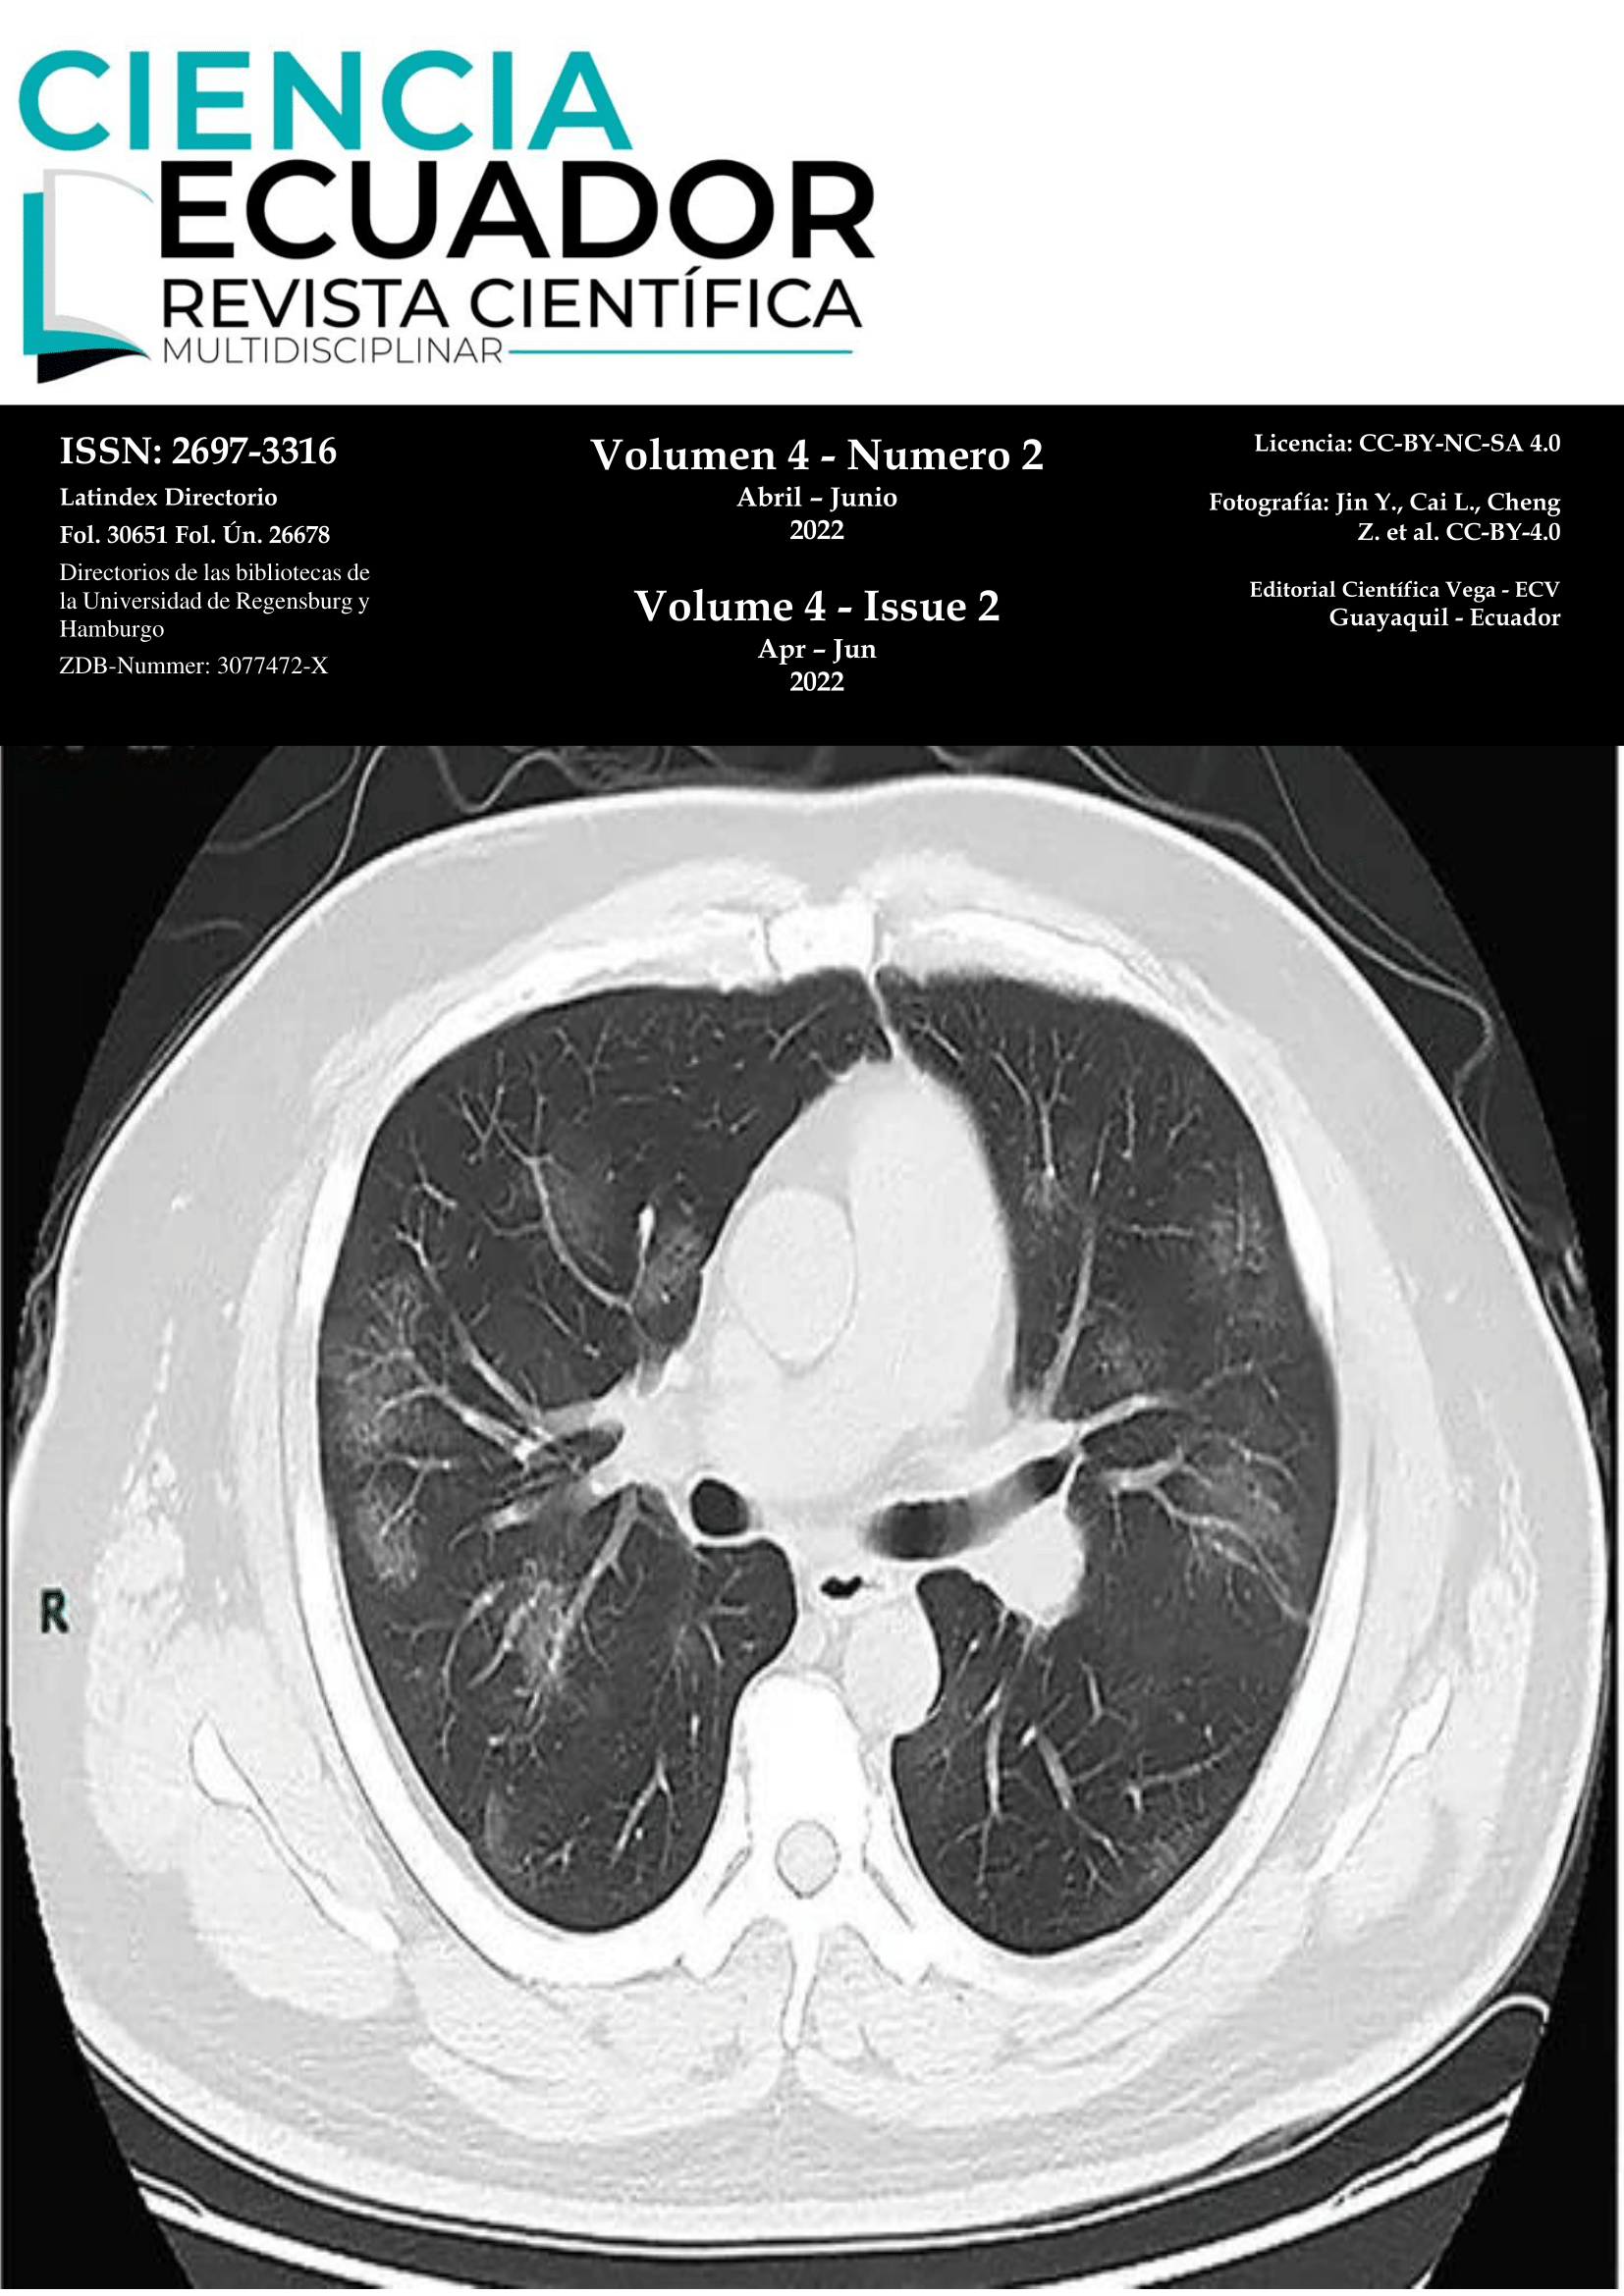

Vol. 4 Núm. 2 (2022): COVID-19

En el presente número presentamos casos de COVID-19.

Evolución tomográfica de paciente con COVID-19

Imagen Médica

Harold Reynaldo Farfán Cano, Stanley Farfán Cano, MD. Mprof., Dr. Richard Bonilla Crespín

1-2